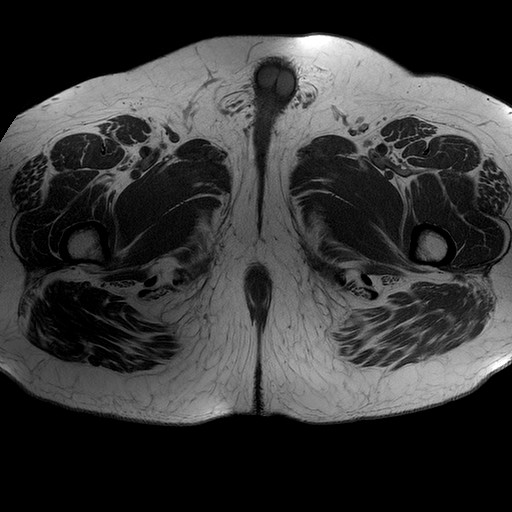

Esami: RMN BACINO

Evidenti e simmetriche alterazioni osteofitosiche in regione coxo femorale con riduzione delle rime articolari. Degenerazione completa del cercine glenoideo. Non attuali segni di versamento articolare. Non segni di edema osseo che escludono attuale algodistrofia od osteonecrosi. Lieve e simmetrica riduzione del trofismo della muscolatura glutea.